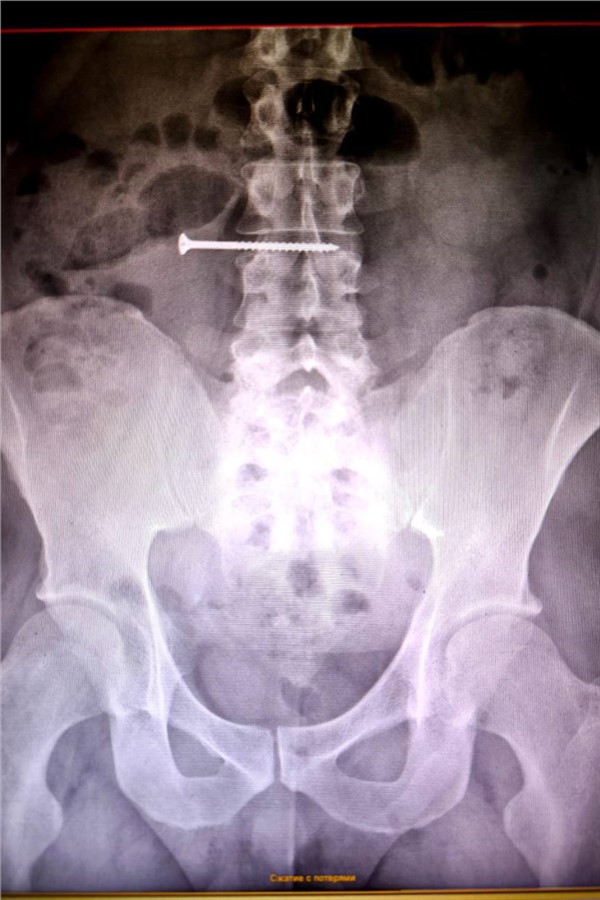

Первичные обследования показали, что пятисантиметровое инородное тело находится в области тонкого кишечника. Ситуация была крайне опасной из-за высокого риска образования сквозного отверстия в стенках органов и развития перитонита.

Пациента экстренно взяли в операционную. Хирурги совместно с врачами-эндоскопистами успешно извлекли саморез. Контрольное эндоскопическое исследование показало, что повреждений стенок желудка и кишечника нет.

Сейчас пациент находится в отделении хирургии под наблюдением медицинского персонала.